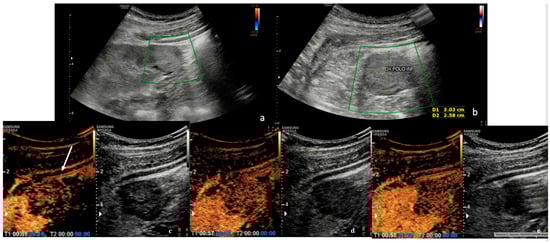

3.1. Ultrasound (US)

3.2. Contrast-Enhanced Ultrasound (CEUS)

| Parameter | Description |

| Topography |

| Morphology/Tumor Borders |

| Enhancement | Dynamic Enhancement: Patterns observed during wash-in and wash-out phases. Degree of enhancement during contrast phases:

| Homogeneity | Uniformity of the contrast distribution after washout: Homogeneous vs. Heterogeneous. |

| CEUS Features | % | n. | p > 0.05 |

| 70.3% | 19 | p < 0.05 |

| 29.7% | 8 | p > 0.05 |

| 0% | 0 | p > 0.05 |

| 52.2% | 12 | p < 0.05 |

| 29.6% | 8 | p > 0.05 |

| 25.9% | 7 | p > 0.05 |

| 62.9% | 17 | p > 0.05 |

| 37.0% | 10 | p > 0.05 |

| 81.5% | 22 | p < 0.05 |

| 11.1% | 3 | p > 0.05 |

| 7.4% | 2 | p > 0.05 |